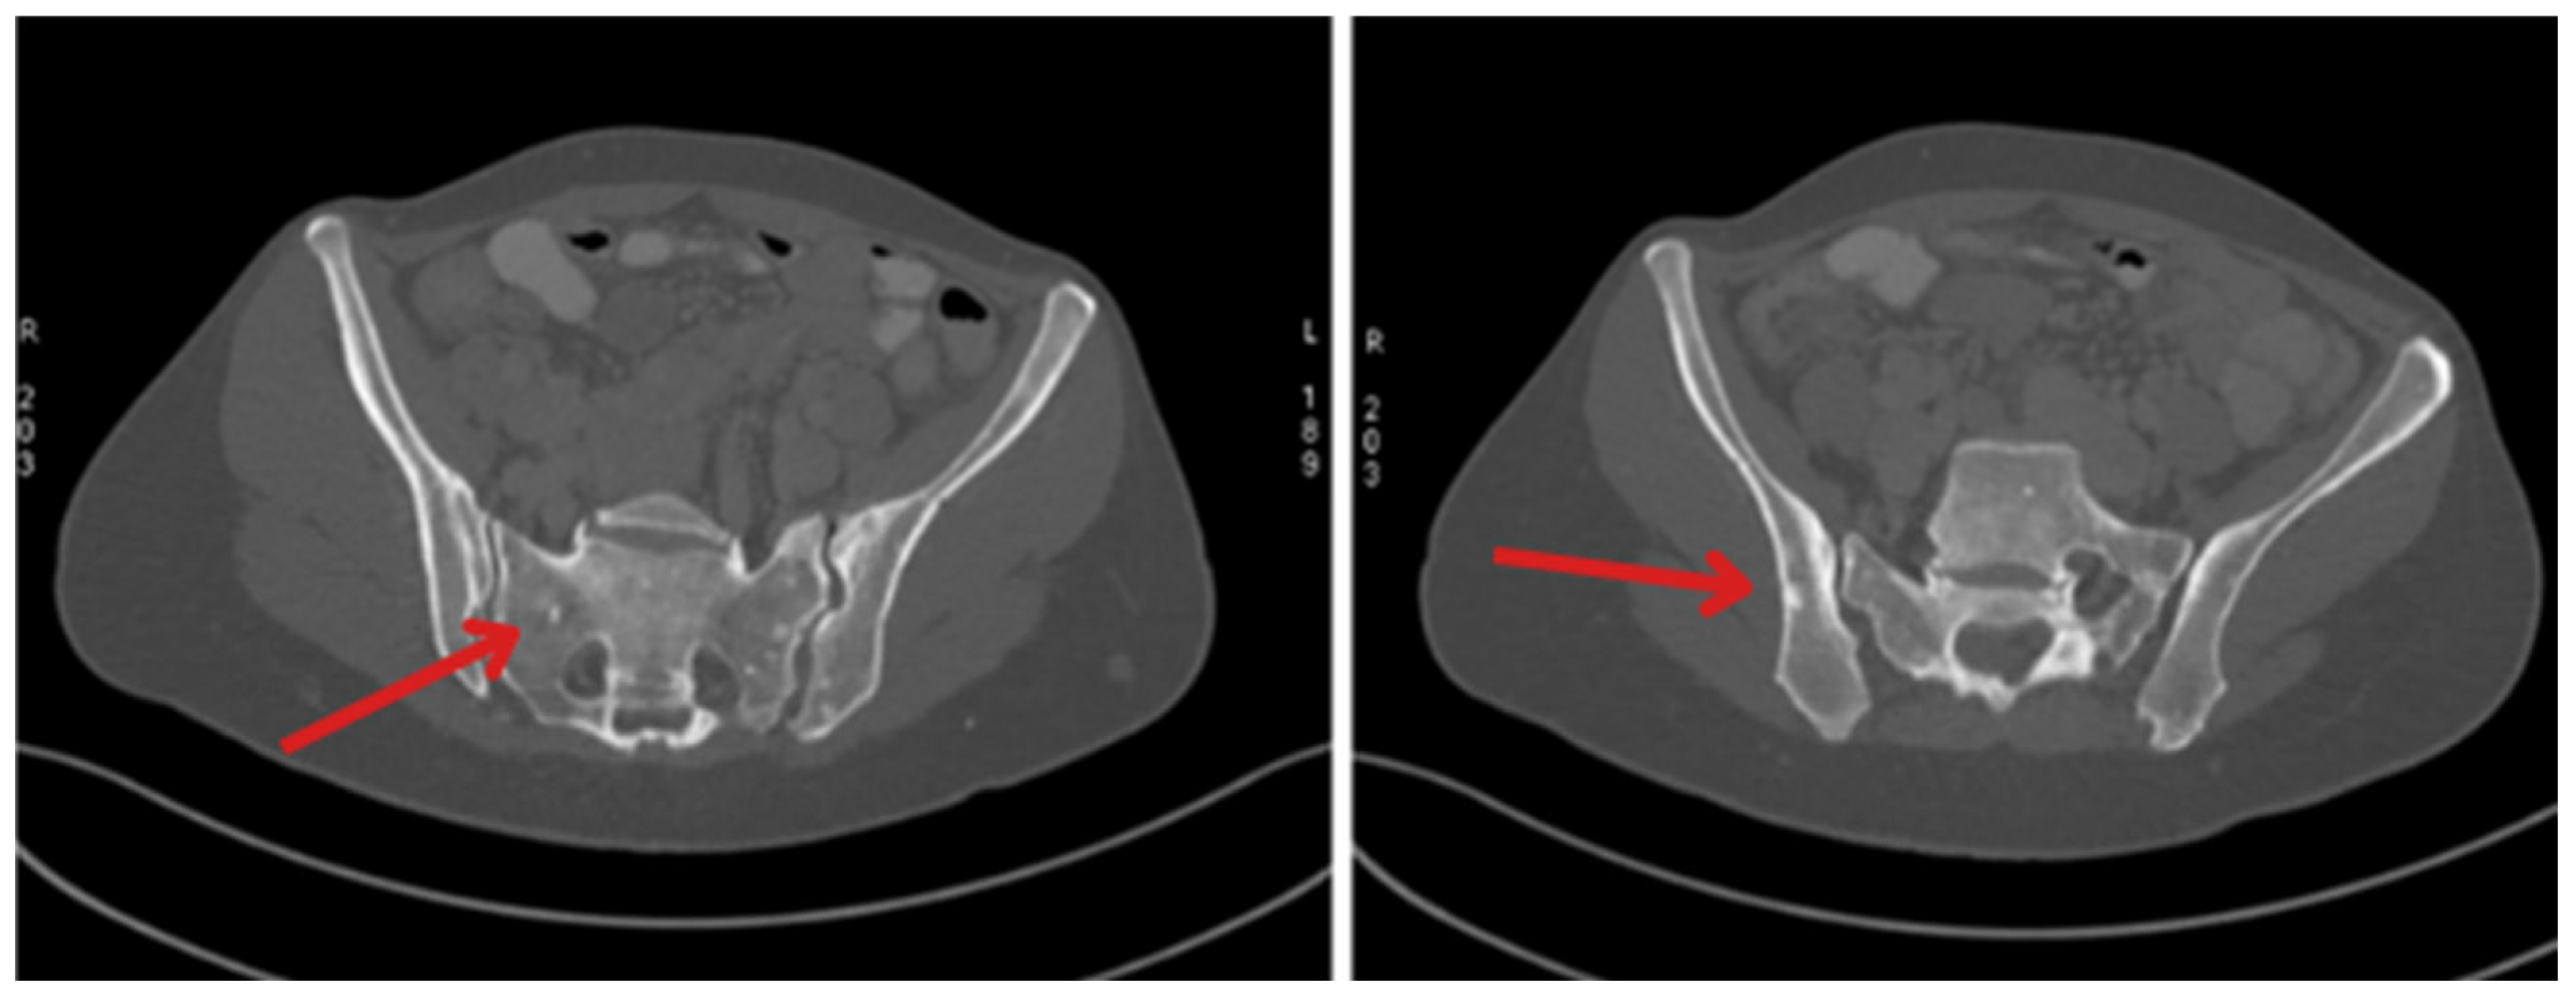

| May 2023 | Beginning of Lutathera treatment CT scan: metastases in the liver, bone sclerosis, enlarged lymph nodes |

| October 2023 | Significant progression of metastases in the liver and bones (spine, ribs, pelvis), and periaortic and pelvic lymphadenopathy The patient was referred to palliative hospice care, resigned from further PRPRT treatment |